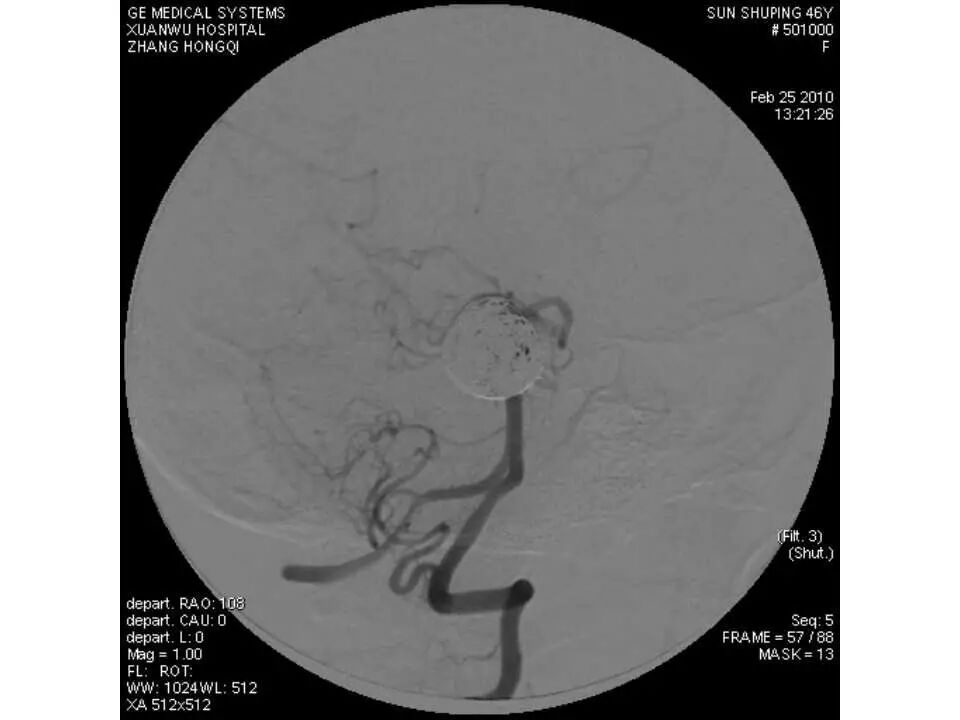

今天为大家分享的是“强生医疗CNV-神经介入专栏”第十五期,由首都医科大学宣武医院何川教授带来的“颅内动脉瘤介入治疗”精彩讲课视频及PPT,欢迎观看、阅读。文章仅代表作者个人观点,如有不同见解,欢迎同道斧正!